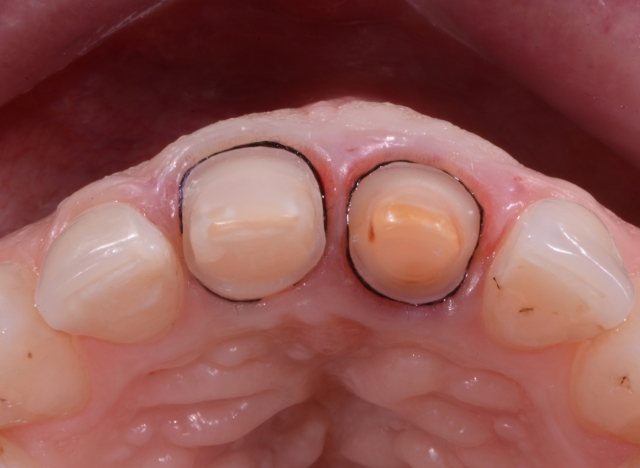

In cases where several abutments are to be imprinted, a definitive path of insertion and removal of the putty is mandatory to facilitate the tray’s reinsertion without distortions of the putty material. Proper parallelism between the prepared teeth is preferred for this technique, and no undercuts are present. To expose the margins of the preparation, a smaller-sized first cord was chosen (000 Ultrapack, Ultradent Products, Inc., USA).

The diameter of the second cord should be chosen according to the amount of deflection needed, considering the gingival biotype. Due to the difference in the positioning of the finishing line into the sulcus, two sizes for the second cords were chosen. Tooth #8 (11) being prepared for a full crown would need more deflection of the soft tissues to expose the preparation margin, so a #0 cord in size (Ultrapack, Ultradent Products, Inc., USA) was chosen. Tooth #9 (21) has been more minimally prepared for a veneer, so a thinner cord #00 would ensure the necessary deflection.